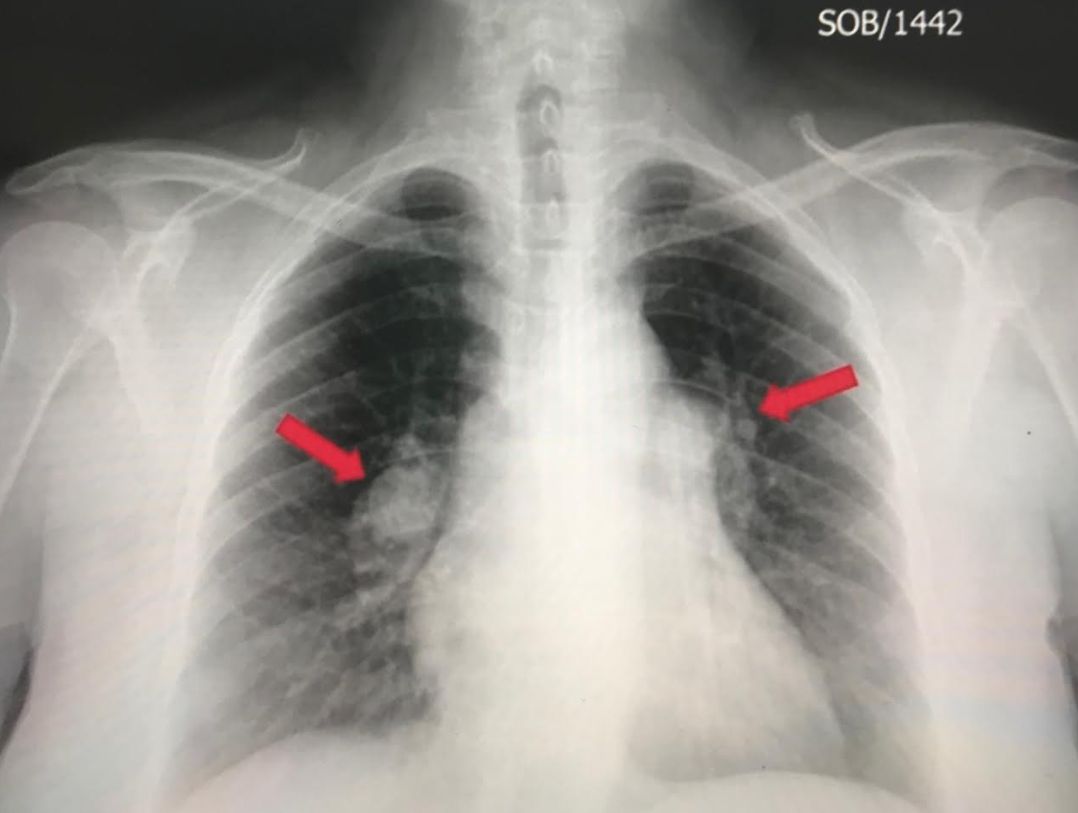

CO-RADS _____ (Equivocal - Features compatible with COVID-19, but also other diseases)

CO-RADS _____ (High - Suspicious for COVID-19)